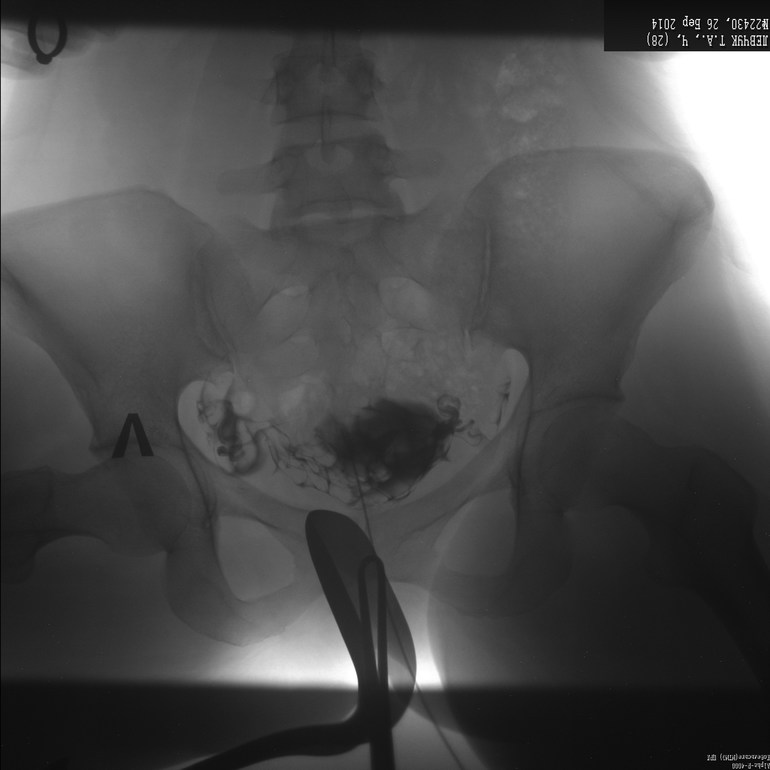

Здравствуйте!Посмотрите снимки, есть ли шанс забеременеть без лапароскопии?

Здравствуйте! Судя по снимкам проходима левая труба, проходимость правой затруднена